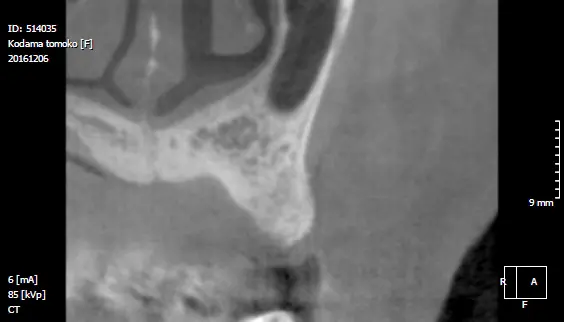

レントゲン写真

| 治療方法 | レントゲンで精査すると歯根が破折しており保存不可能なので抜歯。 もともと正中離開し審美的にも不良であった。正中離開した状態でそのまま治すのかこの際、審美的にも改善したいのか2つのオプションを提示すると矯正治療をした上で完璧に治したいとの要望があったので矯正治療を行いインプラント治療する計画を立てた。両隣在歯3本はジルコニアセラミック審美治療を行った。 |